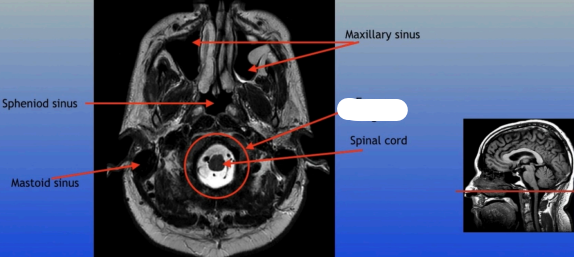

Maxillary Sinus

Sphenoid Sinus

Sphenoid Sinus

Mastoid Sinus

Maxillary Sinus

Spinal Cord